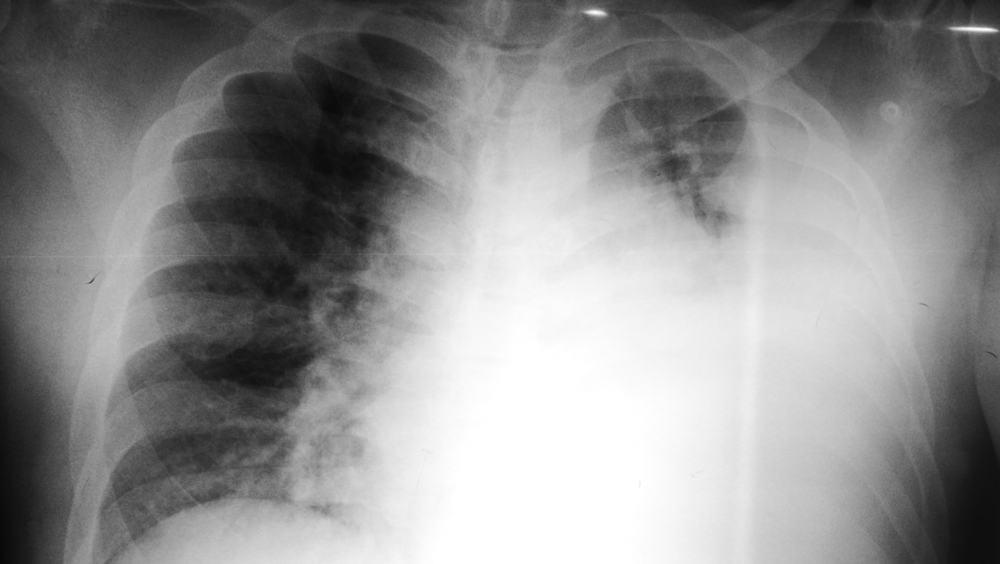

Empiema adalah kondisi yang mungkin terjadi ketika seseorang dengan pneumonia parah tidak membaik meski telah melakukan pengobatan untuk radang paru-paru. Gejala-gejala kemudian juga mulai muncul.

Berikut adalah sejumlah tes yang mungkin diminta dokter untuk mendiagnosis empiema:

Tabung dada biasanya akan tetap di tempatnya sampai hasil rontgen atau ultrasound menunjukkan semua cairan telah terkuras dari dada dan paru-paru bisa mengembang sepenuhnya.